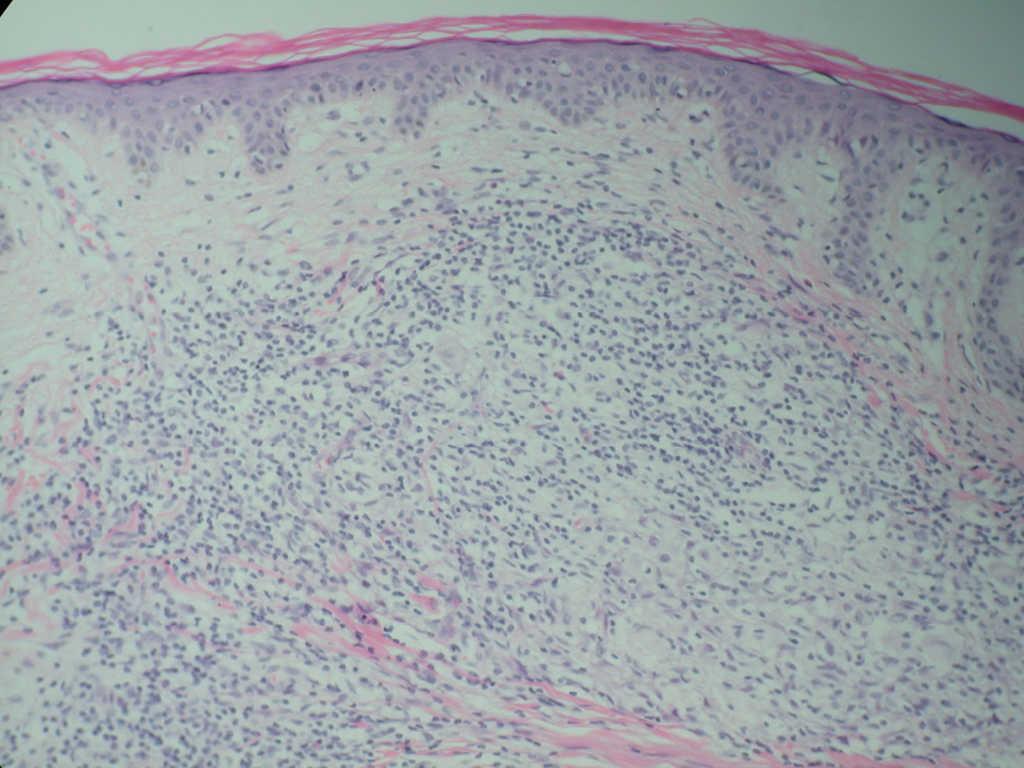

Un varón de 64 años consultó por múltiples lesiones cutáneas, asintomáticas, de 4 meses de evolución, distribuidas simétricamente por el tronco y las regiones proximales de las extremidades. Las lesiones habían comenzado en la región lumbar, en la misma localización de una cirugía previa de hernia discal y habían ido aumentando en número durante las siguientes 4 semanas. No había afectación de cuero cabelludo, palmas, plantas ni mucosas. No había tomado medicamentos ni tenía historia de picaduras de insectos previas a la aparición de estas lesiones. En su historial médico sólo eran relevantes una úlcera gástrica sangrante hacía 11 años y quistes hepáticos detectados por ecografía. A la exploración se observaban múltiples pápulas eritematoparduscas, redondeadas, no confluyentes, de 1 a 3 mm de diámetro. Eran discretas, de ligeramente elevadas a hemisféricas, y firmes a la palpación (figs. 1 y 2). No se palpaban linfadenopatías ni hepatoesplenomegalia. Los exámenes oftalmológicos, pruebas de imagen craneales y torácicas y una ecografía abdominal no revelaron ningún hallazgo patológico. Los estudios de laboratorio que incluyeron análisis de sangre rutinario con hematología y bioquímica, análisis de orina y velocidad de sedimentación eritrocitaria, fueron normales. No se encontró afectación visceral. Se realizó una biopsia (figs. 3 y 4). Los cortes teñidos con hematoxilina-eosina revelaron un denso infiltrado cuneiforme que ocupaba toda la dermis y estaba compuesto por histiocitos, linfocitos y escasos eosinófilos. Los histiocitos contenían núcleos claros y grandes con escasa cromatina y citoplasma vacuolado y mal delimitado. No se encontraron células gigantes. La tinción con azul alcián mostró depósito de mucina en dermis superior. El estudio inmunohistoquímico demostró que las células histiocitarias eran positivas para KP1 (CD68), pero negativas para CD34, S100, CD1a y factor XIIIa, mientras que las células linfocitarias mostraban positividad para LCA. Además, se halló positividad focal para Mac387. La microscopia electrónica no pudo revelar gránulos de Birbeck. Se estableció un diagnóstico de histiocitoma eruptivo generalizado (HEG) teniendo en cuenta criterios clínicos, histopatológicos, ultraestructurales e inmunohistoquímicos.

Fig. 3.--Infiltrado dérmico que muestra histiocitos vacuolados con linfocitos y eosinófilos aislados. (Hematoxilina-eosina, x100.)